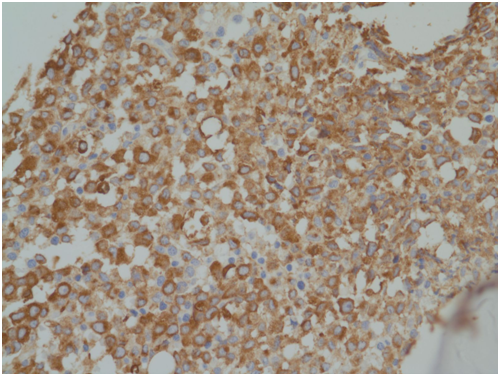

A 14-year-old girl was admitted for neck pain and fever for 5days. Physical examination revealed swelling of left neck. Her blood cell counts were as follows: WBC, 1.59×109/L; Hb,6.7g/dL; and platelet, 68×109/L. Peripheral blood smear showed 4% of blasts. Bone marrow (BM) aspirate showed increased blasts, counted up to 74% of all nucleated cells. The leukemic blasts showed medium to large-size, prominent nucleoli, relatively abundant basophilic cytoplasm with occasional azurophilic granules (Figure 1). BM biopsy showed hypercellularity with diffuse infiltration of blasts (Figure 2). The leukemic blasts were immuno histochemically reactive for myeloperoxidase (MPO) (Figure 3). Flow cytometric analysis showed leukemic cells positive for CD13, CD33, CD64, CD11c, HLA-DR, cMPO and CD7, and negative for CD34 and terminal deoxynucleotidyl transferase (TdT). A cytogenetic study revealed the following chromosome abnormalities: 46, XX, t(5;11)(p12p15.3;q13q23), t(8;12)(q22;q13), add(14)(p12),-17, +mar[10]/46, XX[10] (Figure 4). In addition, interphase fluorescence in-situ hybridization (FISH) analysis using a MLL LSI dual color, break-apart probe demonstrated 76% of cells with break-apart signals (Figure 5). FISH study for EGR1/D5S23showed normal pattern on interphase cells; however, one D5S23 (5p15.2) signal was observed at chromosome 11 on metaphase cells (not shown). These results could be suggestive of t(5;11) with four-break rearrangement, which correlate with chromosomal results. Recurrent gene rearrangements in acute leukemias by multiplex reverse transcriptase-polymerase chain reaction (RT-PCR) including major and minor BCR/ABL1, PML/RARA, and RUNX1/RUNX1T1 genes was negative. FLT3-ITD, NPM1, and KIT mutation tests showed negative results. Based on above findings, the patient was diagnosed as having acute myeloid leukemia with variant MLL translocation. Concurrent neck computed tomography (CT) scan revealed diffuse superficial and deep infection of left neck with bilateral cervical lymphadenopathy. Chemotherapy was scheduled, but withheld due to persisting high fever. On follow-up CT scan, abscess formation of left neck was suspected. Despite intensive antibiotic and supportive therapies, the patient succumbed due to septic shock 28 days after admission.

Figure 3 Blast cells with positivity for myeloperoxidase (MPO stain,×400).